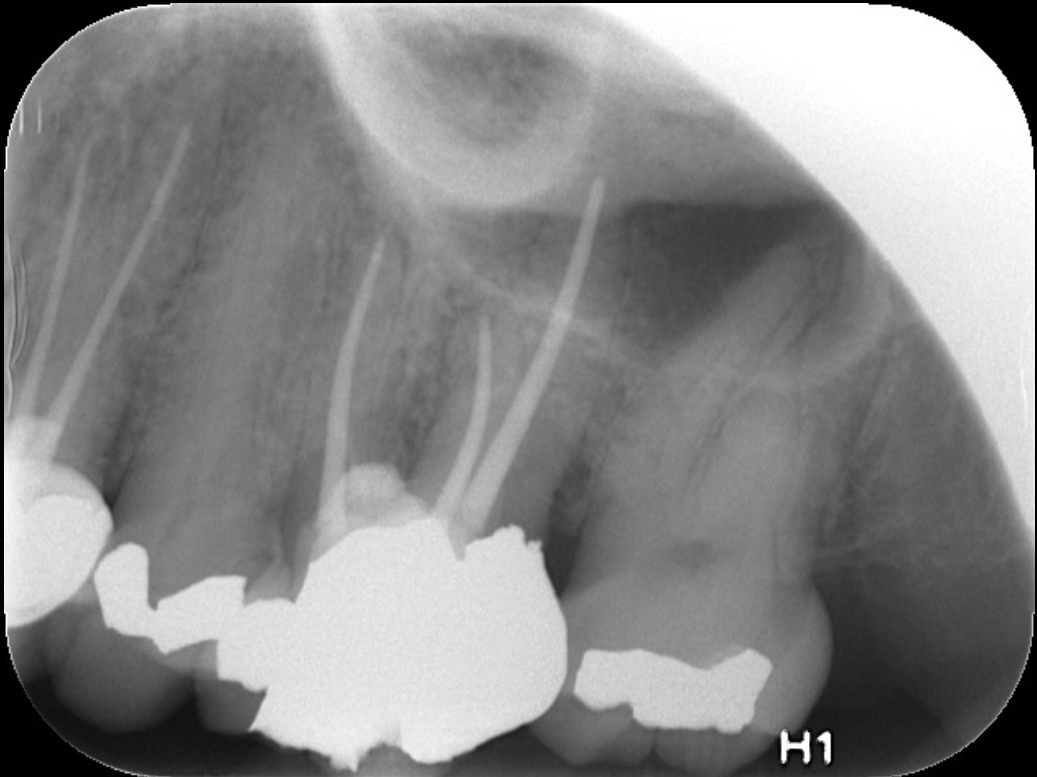

Fig 9 Preoperative radiographs showing mesial perforation.

Figure 9

Fig 10. Preoperative radiographs showing mesial perforation.

Figure 10

Clinical procedure: Once a perforation occurs, the extent of the perforation must be assessed. If there is an adjacent bony defect, the bony defect should first be filled with an osteoconductive or osteoinductive material. This can be done with a bone graft, calcium sulfate, or collagen/gelatin sponge. The dentinal portion of the tooth that has been perforated is then restored with MTA (Figure 9 through Figure 14).